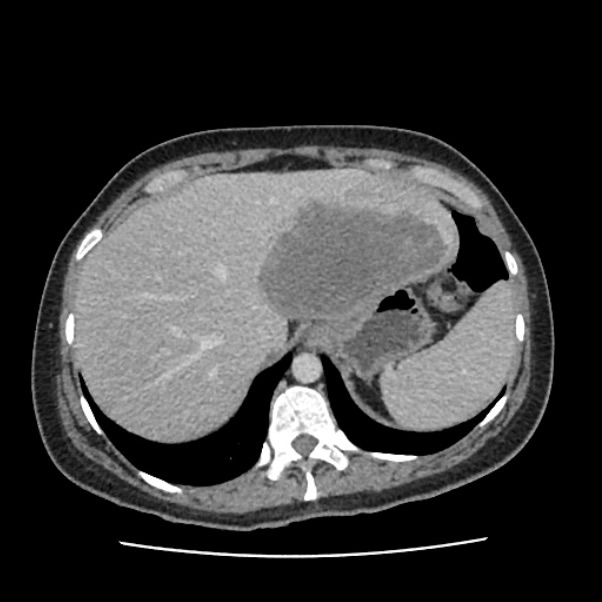

Mujer de 41 años con fiebre sin foco